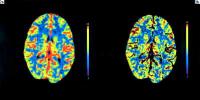

Abbildung 2: Die Kontrolluntersuchung (sechs Tage nach Rückbildung der Hemiparese) zeigte ein komplett normales Perfusionsmuster mit Normalisierung des CBV (a) und des CBF (b).